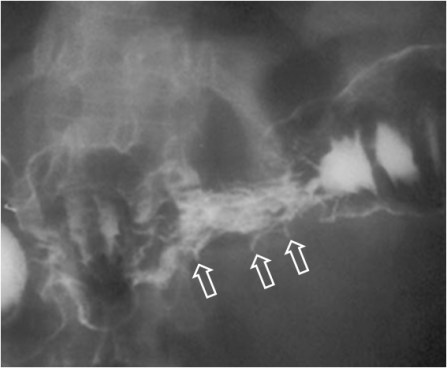

Los implantes metastásicos en la serosa del colon producen una reacción desmoplásica causante de la rigidez y retracción de la pared del colon, que se manifiesta por estrías o pliegues transversales en el colon, en el estudio con doble contraste (flechas).

Esta imagen muestra la afectación similar en un asa de intestino delgado.